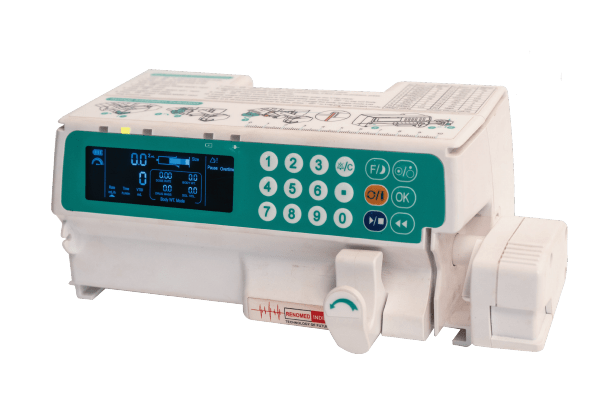

INFUSION PUMP

INFUSION PUMP

SYRINGE PUMP

SYRINGE PUMP

SP750 Infusion Pump

SP750 Infusion Pump